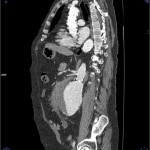

Para valorar la afectación en longitud la mejor prueba para hacerlo es la reconstrucción (MRP) , en planos sagital y coronal. Con las imágenes obtenidas en el TAC se hace una reconstrucción de todas obteniendo una imagen en un plano sagital y coronal. Con esta vista podemos ver la longitud y el diámetro exacto de la rotura del aneurisma y de de las zonas afectadas.

En la reconstrucción (MRP) en planos sagital y coronal se obtienen las siguientes imágenes: